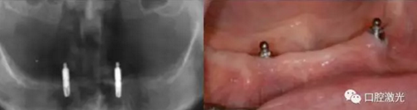

#33,#43顯示存在種植體周圍炎

激光對#43病變組織氣化切除前(左圖)后(右圖)

激光對#33病變組織氣化切除前(左圖)后(右圖)